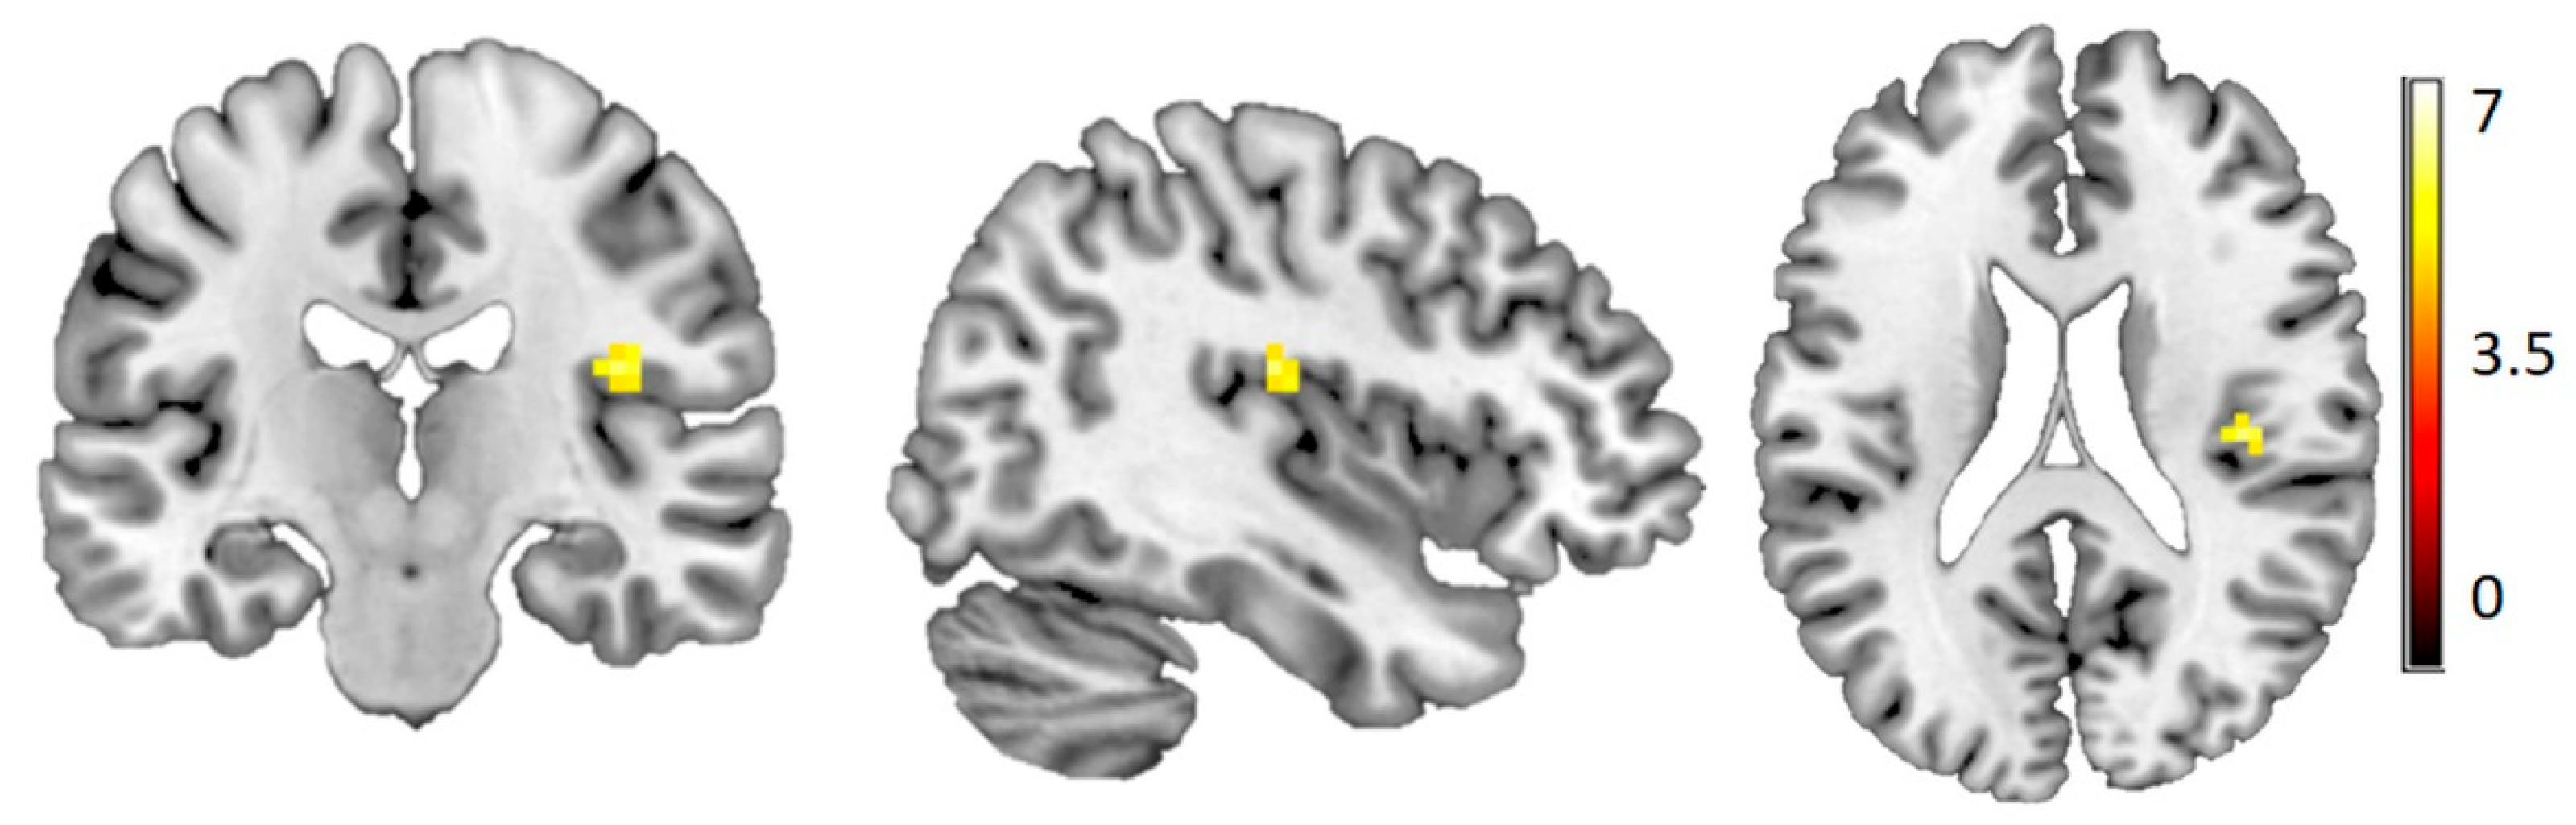

3.4. Voxel-Based Morphometry

4. Discussion

4.3. VBM